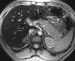

CT scanning is neither sensitive nor specific for the detection of mild hepatic iron overload. MRI may be more sensitive than CT scanning, but this modality has not been validated as a diagnostic test to help confirm hemochromatosis. Hepatic iron quantification with MRI might be helpful. [6]